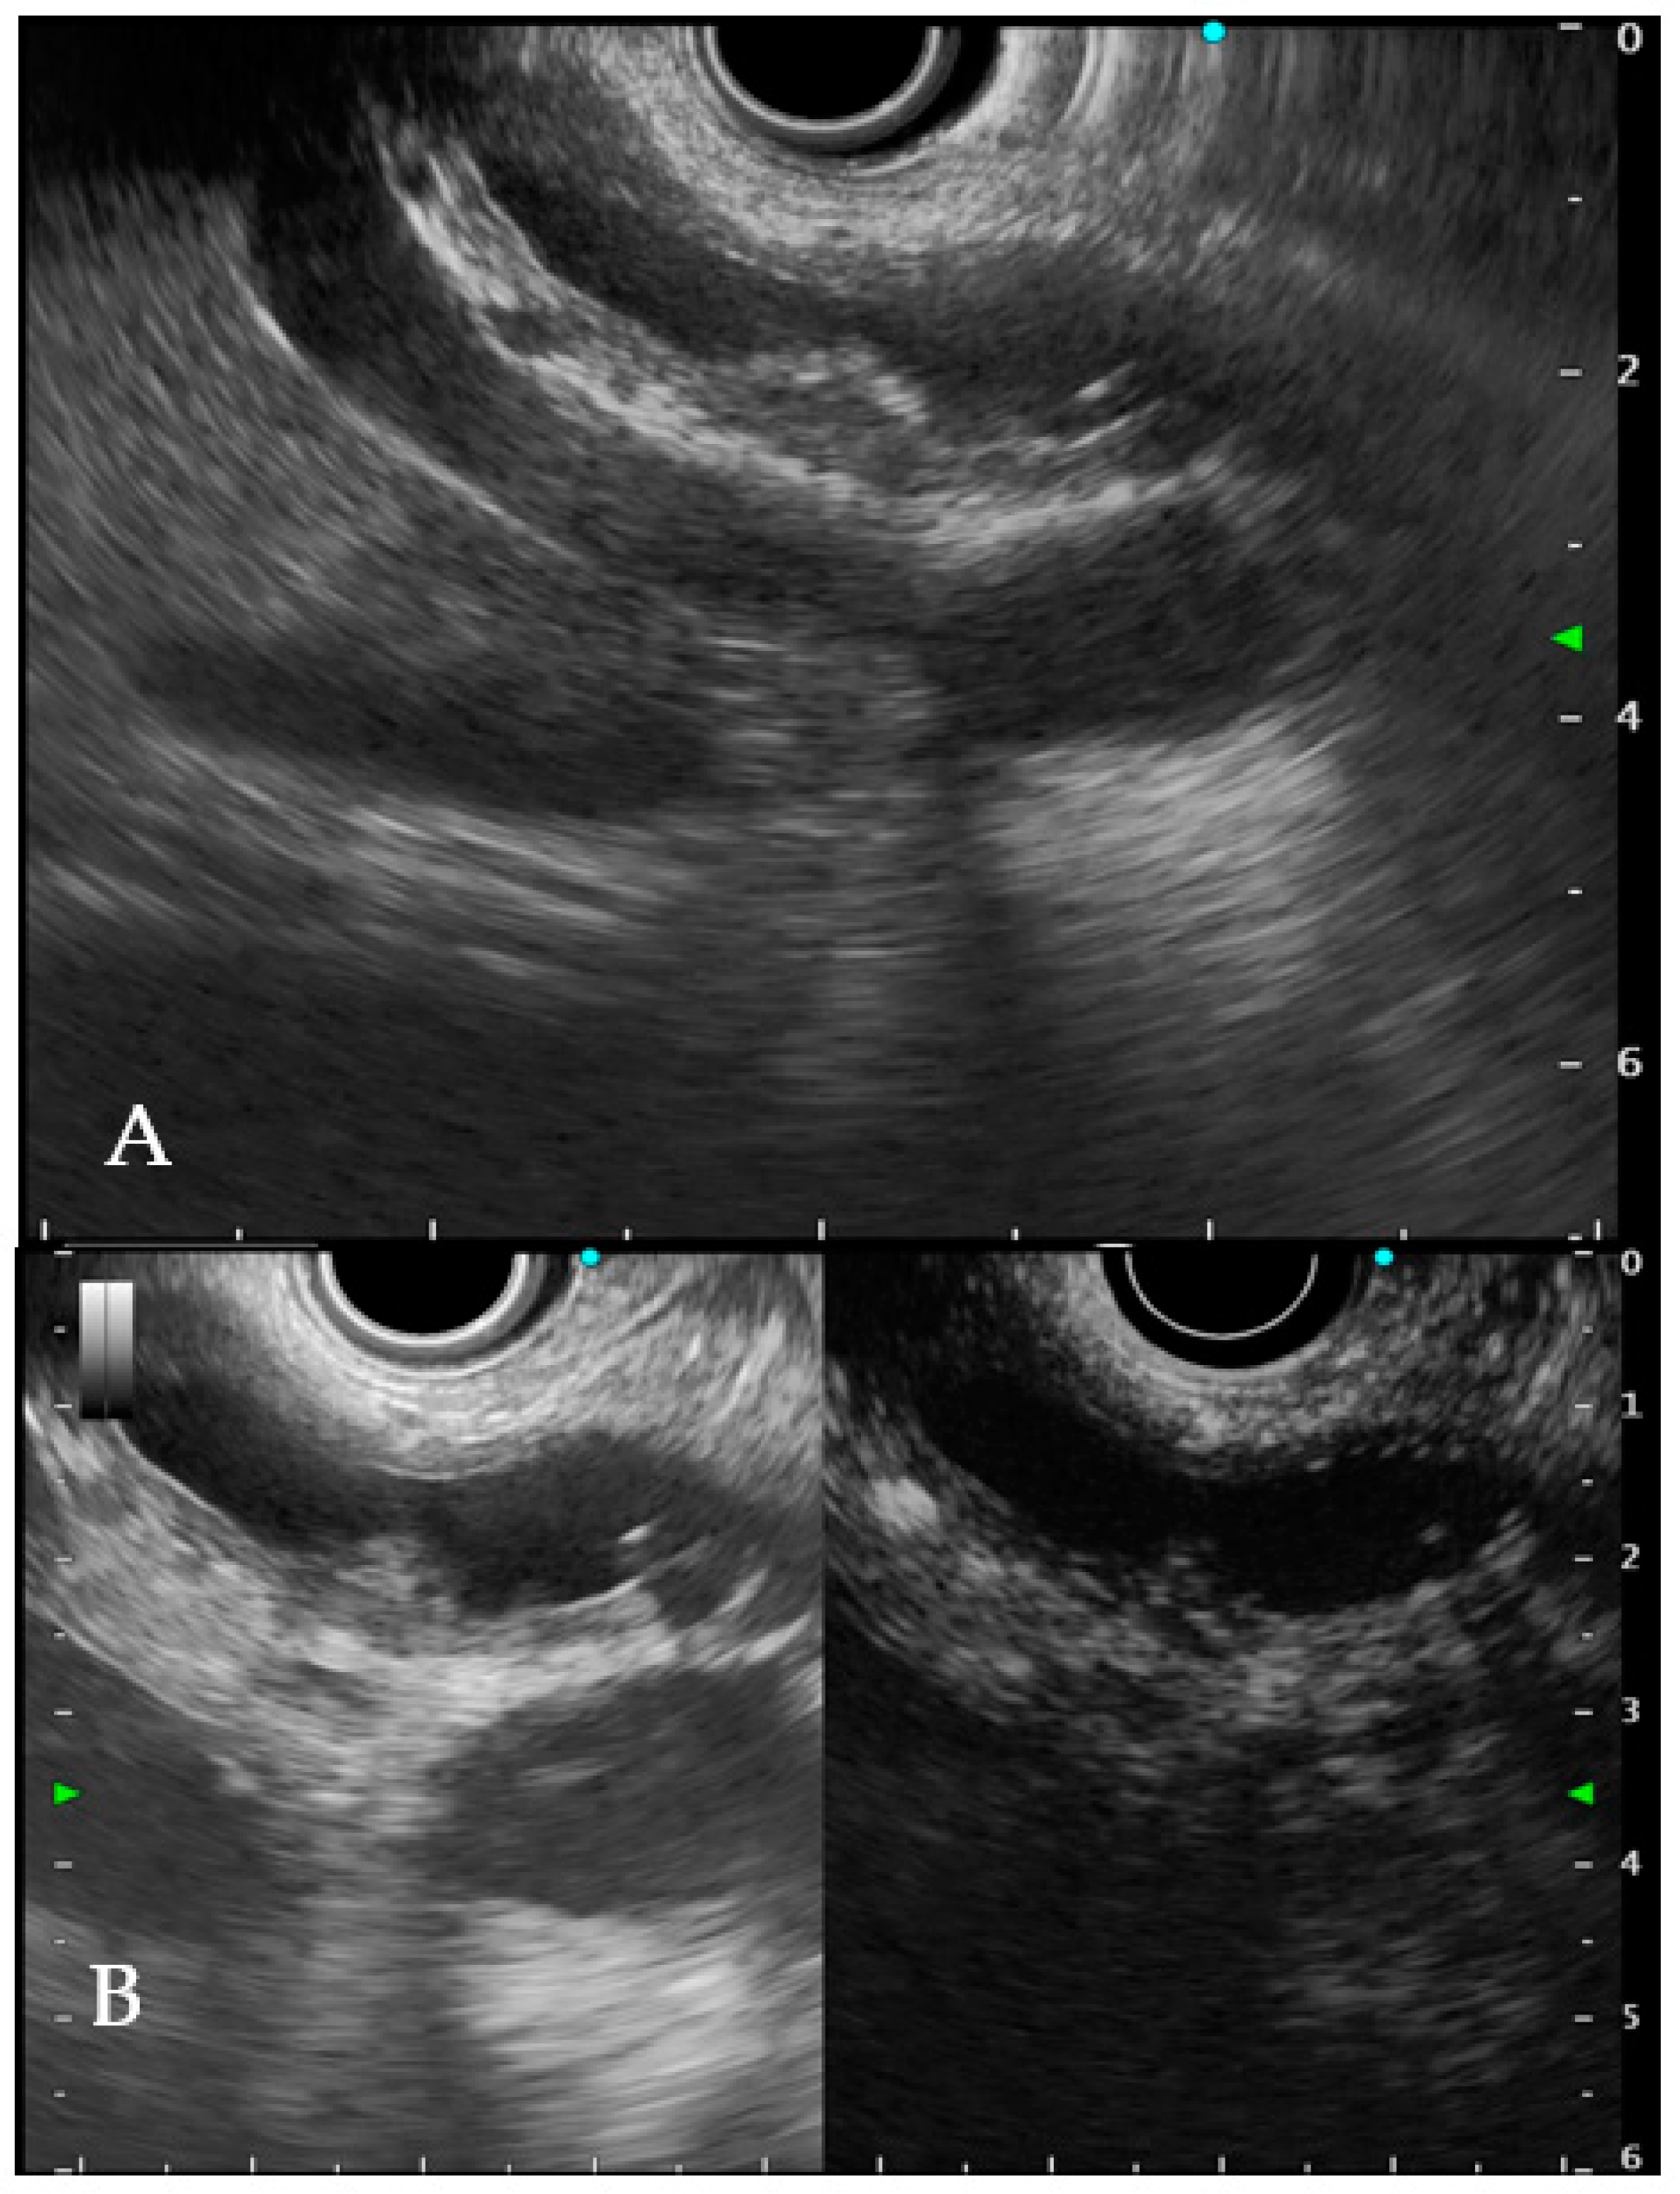

6.1. Intraductal Ultrasonography

6.2. Endoscopic Ultrasound